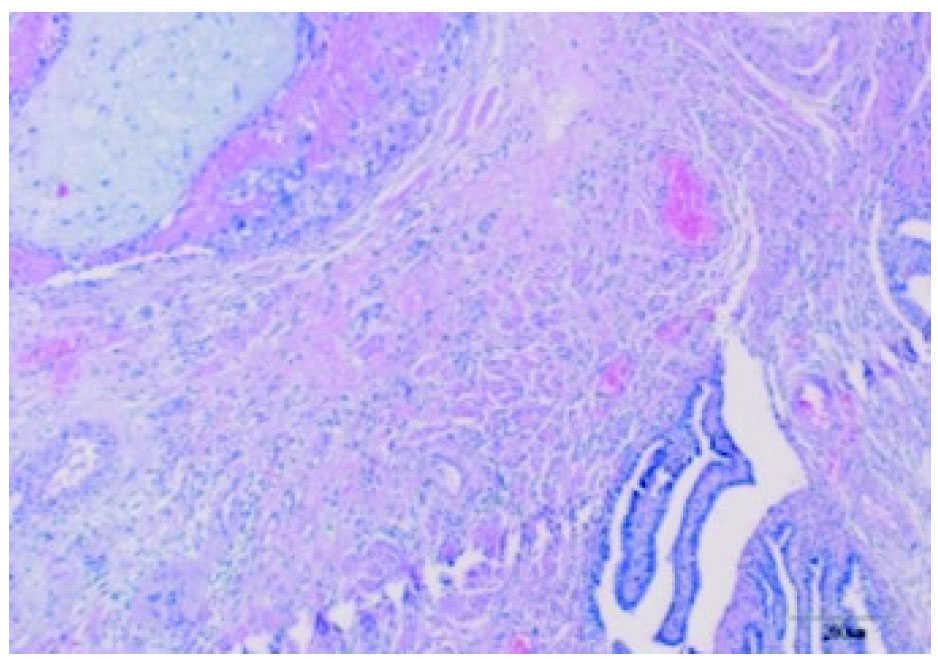

La anatomía patológica reveló en el tejido adherido al epiplón la presencia de células trofoblásticas y vellosidades coriales junto a restos hemáticos (fig. 3); en la trompa derecha se observaba la misma imagen (fig. 4) y la izquierda no presentaba alteraciones.

Figura 3. Anatomía patológica del tejido que se encontraba adherido al epiplón, en el cual aparecen células trofoblásticas y vellosidades coriales junto a restos hemáticos.